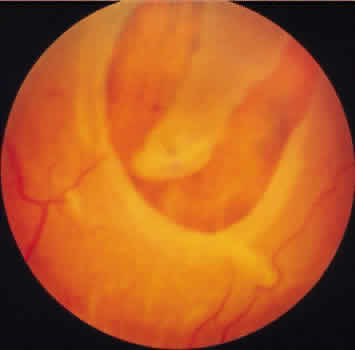

FULL-THICKNESS RETINAL TEAR

A full-thickness retinal tear is a complete traction-related break in the sensory retina. The tear is usually U or V shaped with the broad base directed anteriorly, a tapered flap extending into the vitreous, and condensed vitreous strands attached to the apex and inner surface of this flap (Figs. 42 to 44). In some instances, the flap is partially or completely avulsed and can be identified as a free operculum in the overlying vitreous. This free operculum retains its attachment to the vitreous body, and it is almost always located anterior to the retinal tear (Fig. 45). As time passes, the margins of the retinal tear become smooth or rounded and the retinal flap becomes shrunken and degenerated. Seen through the retinal break, the retinal pigment epithelium often appears stippled or granular.

Fig. 42. Tears in nasoinferior quadrant of peripheral retina of a 76-year-old man. Large full-thickness tear has shriveled flap (arrow) to which vitreous fibrils are attached. There are many small partial tears of the surface of adjacent retina, most notable along vessels. (× 8.)

Fig. 43. Flap of large full-thickness retinal tear shows microcystic degeneration; it is attached to condensed hyaloid of the posteriorly detached vitreous body. Posterior hyaloid also contains fragments from surface of the underlying retina, corresponding to partial retinal tears (arrows) behind the full-thickness retinal break. (× 150.)

Fig. 44. Tractional full-thickness retinal tear with avulsed retinal blood vessel (white arrow). Edges of tear are beneath the elevated retinal flap (black arrows)

Fig. 45. Retinal tear at equator of eye of a 48-year-old woman. Avulsed spheric fragment of retina (operculum; arrow) is subtended over round full-thickness retinal break. (× 5.5.)

Full-thickness retinal tears unassociated with lattice degeneration, cystic retinal tuft, zonular-traction tuft, or other identifiable retinal abnor-mality are likely to occur at sites of exaggeratedparavascular vitreoretinal attachment and along the posterior border of the vitreous base. When posterior vitreous detachment occurs, full-thickness as well as partial-thickness tears may occur at one or more of these locations.

On histologic examination, full-thickness retinal tears demonstrate vitreous attachment to the degenerated retinal flap or free operculum, gliosis and degeneration adjacent to the smooth, rounded margins of the tear, a variable degree of associated retinal detachment, and a combination of cell breakdown and hyperplasia in the underlying retinal pigment epithelium.27

Retinal breaks occur in about 13% to 14% of autopsy cases.40 Excluding retinal tears at the ora serrata and tears related to lattice degeneration or other identifiable disease processes, full-thickness retinal tears are found in 12% of adults at autopsy, are bilateral in 5% of affected adults, and are present in 7% of adult eyes (see Table 3). These lesions are most prevalent in the inferior temporal quadrant, are always located posterior to the vitreous base, and are universally associated with posterior vitreous detachment. Approximately half such full-thickness retinal tears are associated with at least a localized retinal detachment; this is especially likely to be present where the tear is located in the superior temporal or superior nasal quadrant.

Clinical identification of full-thickness retinal tears is particularly significant. In the presence of posterior vitreous detachment, attention may be focused on abnormal retinal areas by a free operculum, projecting retinal flap, hemorrhage, or localized retinal pigment epithelium alteration.41

With or without these diagnostic clues, full-thickness retinal tears are visible on contact-lens biomicroscopy or on indirect ophthalmoscopy and scleral depression. As the scleral depressor creates translucency in the adjacent sensory retina, the tear is seen as a contrasting red area. A retinal tear and a retinal hemorrhage may be differentiated by the fact that the intensity of the contrasting red color of a tear varies with the position of the scleral depressor, but the red color of a retinal hemorrhage is unaffected by movement of the depressor. Full-thickness retinal tears should be carefully evaluated because these tears often warrant prophylactic therapy in an effort to prevent retinal detachment, and they require treatment when associated with rhegmatogenous retinal detachment.